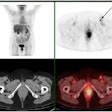

FDG-PET/CT contributes to anal cancer follow-up

September 14, 2017